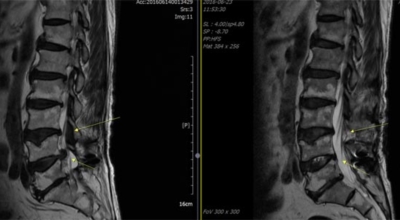

정상인 사람은 척추가 완만히 휘어져 있는데 척추관 협착증인 사람은 더 일자로 펴져 있고 정상인 사람의 척추관은 공간이 적당한데 비해 척추관척 협착증인 사람은 척추관이 일그러져 있어요. 척추관 협착증 환자는 자기 공명 영상(MRI)에서 보면 척추관 내 신경을 싸고 있는 경막 안에 정상에서 보이던 뇌척수액이 보이지 않는다는 특징이 있어요.